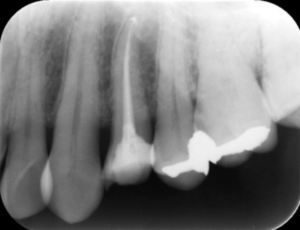

BEFORE

AFTER

基本情報

| 年齢・ 性別 |

31歳・女性 |

|---|---|

| 主訴 | 左下が欠けて穴が空いた 左下6番 |

| 治療 内容 |

左下6番根管治療 |

| 治療 期間 |

約1ヶ月 |

| 治療費 | 来院回数4回 約4,000円(保険診療3割負担) 別途CT代約4,000円(保険診療3割負担) (2024年11月現在) |

| リスク・副作用 | ・神経の治療の刺激により、数日痛み・腫れがでる可能性があります。 ・細く繊細な器具を使用するため、器具が破折する可能性があります。 ・複雑な神経の治療では、大学病院もしくは専門医による治療が必要となることがあります。 ・または抜歯になることもあります。 |

| 治療方針 | 左下6番の歯に穴があき、虫歯が進行していたため根管治療となりました。 |

| 特記事項 | 根が4本あるためCTを撮影し根の形を詳しく確認したところ、そのうちの2本が途中で癒合し根が細くなっていました。 根管が細く癒合もあるため、細く曲がった歯の神経の治療に対応できる弾力が高く柔軟性のあるニッケルチタンファイルを使用。 またラバーダムを用い防湿を行いながら治療を進めました。 |

| 担当者所見 | 今後コア(土台)を入れ被せ物をセットし治療終了となります。 また、引き続き他の虫歯治療を進めていきます。 |